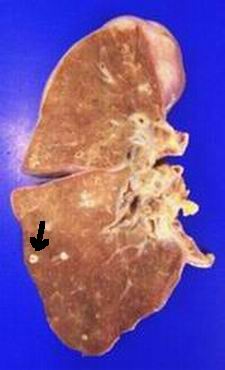

Figura 5 - <div style=fiogf49gjkf0dFotografía macroscópica del pulmón derecho al corte en la que se observa señalado con flecha negra un pequeño nódulo blanquecino correspondiente a diseminación metastásica de la neoplasia.">

Figura 5 -

fiogf49gjkf0d

Fotografía macroscópica del pulmón derecho al corte en la que se observa señalado con flecha negra un pequeño nódulo blanquecino correspondiente a diseminación metastásica de la neoplasia.

Respecto al pulmón derecho, éste muestra externamente pequeñas nodulaciones blanquecinas de 0,5 cm. de diámetro y de consistencia firme que, al corte seriado, se encuentran difusamente distribuidas por los tres lóbulos del pulmón derecho (Figura 5) y el superior del izquierdo, siendo las adenopatías hiliares de aspecto no neoplásico